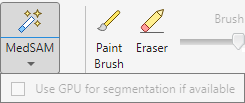

On the app toolstrip, in the Draw tab, select MedSAM. You can use a GPU, if available, for faster segmentation by selecting Use GPU for segmentation if available. This option is selected by default if a GPU is available, but you can choose to clear it. If a GPU is not available, the option is inactive.